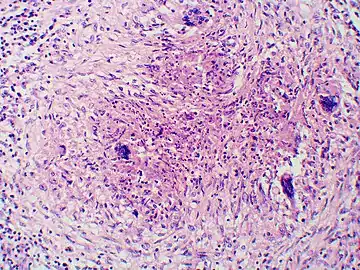

Granuloma with early suppuration. Fungal organisms difficult to recognize at this low magnification.

Large yeast-like fungi seen within giant cells at arrows.

Large yeast-like fungi seen within giant cells at arrows. Budding yeasts in cytoplasm of giant cells at arrows. Broad-based budding and double contoured cell wall seen in the giant cell in the center is characteristic of Blastomyces dermatitidis.